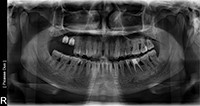

استخوان های خودبخود تولید شده که از استئوتومی پیشین تشکیل شده اند، با مقدار کمی از مواد پیوندی کورتیکو اسفنجی (Raptos (Citagixix)) مخلوط شده و با یک قاشق جراحی کوچک پدالی به استئوتومی معرفی می شوند(Zoll-Dental) (شکل 9). دو ماکرو ایمپلنت 6.0 در 6.0 میلیمتر در محل های آماده شده با استفاده از گیرنده های Ultim متصل می شوند (شکل 10). به محض قرارگیری، حامل ها برداشته شدند و ایمپلنت با یک آچار پیچی در جای خود ثابت شد. به محض رسیدن به کف نازک سینوس و به طور مکانیکی فشار به آن، یک تخلیه کنترل شده منجر به ایمپلنت در ناحیه شماره 2 شد (شکل 11).

مقاومت چرخش 45 نانوسانتیمتر بر روی ایمپلنت شماره 2 و 47 نانوسانتیمتر بر روی ایمپلنت شماره 3 در جاگذاری نهایی به دست آمد. این مقادیر به خودی خود پایداری اولیه ی کافی را برای بارگیری سریع ایجاد می کنند، اما هر دو ایمپلنت با استفاده از RFA (Osstell) مورد بررسی قرار گرفتند (شکل 12). مقدار ثبات ایمپلنت (ISQ)68 و 72 برای سایت های شماره 2 و 3 به دست آمد. به طور کلی پذیرفته شده است که مقدار ISQ بالاتر از 65 برای شروع یک پروتکل بارگیری ایمپلنت (یا بارگیری اولیه) برای خلاصه تحقیق توسط Osstell کافی است.

شکل 11. رادیوگرافی پانورامیک ایمپلنت در محل.